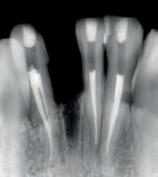

We recommend the following steps for professional whitening evaluation and treatment.

Evaluate the origin of tooth staining and check for restorations that could affect the final result (use X-Ray if needed). Assess the intention of whitening system (cosmetic for generic “day-by-day” discoloration; medical devices for teeth discolored by disease, injury or medical treatment). Consider amending your periodical medical history by adding a question about the patient’s satisfaction with their oral esthetics. Explain to the patient that restorations will not whiten, and discuss the possible need for new restorations after whitening. Check existing sensitivities, and perform an adequate treatment before starting a whitening procedure. Pregnant or breastfeeding women should not whiten. Patients with serious health concerns should consult their primary care provider prior to treatment. Cosmetic teeth whitening treatments are not permited under the age of 18.

Determine origin of staining, evaluate gingival and dental health. Check for restorations in the esthetic zone that may not match after whitening. Discuss changing them out or resurfacing after whitening.